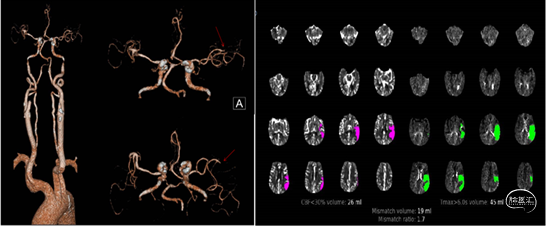

患者男性,54岁,因突发头晕8小时入院。既往体健,否认高血压病,糖尿病病史。患者于8小时前晨起活动后突发头晕,伴恶心,无呕吐,卧床休息后上诉症状未见缓解,随后患者逐渐出现言语含糊,吐字不清,家属发现后急送来院。

查体:血压130/90mmHg,心肺未见异常。专科查体:神清,构音障碍,双侧瞳孔等

大等圆,光反射灵敏。口角略歪斜,四肢肌力5级,肌张力正常,双侧病理征(-),NIHSS评分4分。急诊CT示左侧椎动脉高密度征。CT示右侧小脑陈旧性梗死。

初步诊断:脑梗死(后循环,不明原因)。

患者以头晕为首发表现,随后症状逐渐进展,发病8小时,CT未见出血,考虑新发梗死可能性大,因错过静脉溶栓时间窗,遂完善头核磁MRI+MRA评估颅内情况。

急诊核磁DWI示左侧小脑及延髓新发梗死。

MRA示左侧椎动脉颅内段闭塞,闭塞段呈杯口征。

结合患者CT及核磁影像,考虑患者左侧椎动脉颅内段系急性闭塞,闭塞端呈杯口征,栓塞可能性大。向患者家属详细交代病情,考虑栓塞可能性大,因患者基底动脉走形较直,考虑血栓可能骑跨位于左侧小脑后下动脉及椎基底汇合部,有继续向远端脱落导致基底动脉闭塞风险。

分析造影考虑患者原先血栓符合术前判断,骑跨位于小脑后下动脉及椎基底动脉汇合部,在搬动过程中,椎基底汇合部血栓再次崩解移位,最终左椎颅内段通畅,但左侧小脑后下动脉闭塞,右侧大脑后动脉远端血栓异位。

考虑患者年轻,左侧椎动脉优势,左侧小脑后下动脉供血范围较大,若不能及时开通血管,可能导致小脑大面积梗死,后继出现脑水肿,脑疝几率较大,向患者家属交代手术风险后家属积极要求介入治疗。

快速建立8F导引导管+CAT6中间导管建立路径,微导丝携微导管顺利通过左侧小脑后下动脉闭塞段。4/20取栓支架输送到位下图2;释放取栓支架下图3;取栓支架释放后造影血管未再通下图4。

等待5分钟后,部分回收微导管,钳夹血栓,上送中间导管,采用SWIM技术取栓,一次钳夹取出的暗红色血栓。复查造影见左侧小脑后下动脉完全再通。